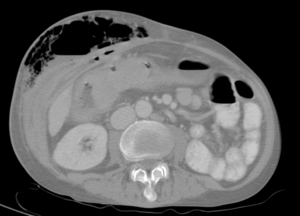

| Abdominal CT with right colocutaneous fistula and associated subcutaneous emphysema. | |

الناسور القولوني المثانيcolovesical fistula

هو ناسور مكتسب غالباً يحدث تالياً لآفة أخرى، قد تكون التهابية كما في داء كرون Crohn أو داء الرتوج السينية (الرتاج) diverticulosis التي يؤدي التهابها وتشكّل خراج يلتصق بالمثانة إلى حدوث اتصال مع المثانة عبر فوهة صغيرة، أو يكون السبب ورماً في السيني sigmoid أدى تنخره إلى حدوث هذا الاتصال، كما قد يتلي التعرض للأشعة في حالة المداواة، أو ينجم عن رض جراحي بعد العمليات المجراة على الموثة (البروستات) أو القولون السيني أو المستقيم.

يتظاهر هذا الناسور سريرياً بخروج فقاعات غازية مع البول وبحدوث التهابات بولية متكررة.

يتم وضع التشخيص الأكيد عن طريق التصوير الطبقي المحوري CT.Scan.